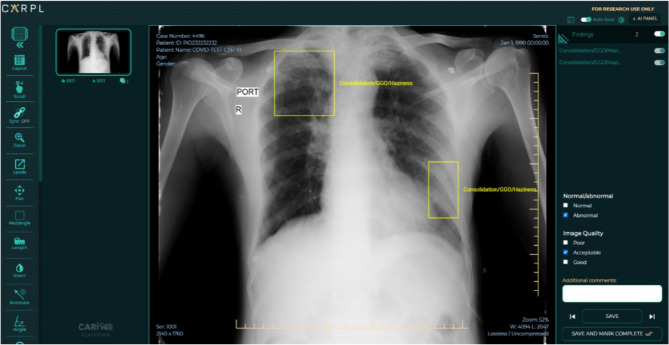

Furthermore, the CovBaseAI model can also be used as a diagnostic tool for SARS-CoV-2 infection or confirmed COVID pneumonia, we used a testing dataset which comprised of a total of 905 CxRs acquired from Mahajan Imaging, Delhi. These 905 CxRs comprised of 434 RT-PCR positive scans and 471 historical scans that were acquired before the worldwide outbreak of COVID-19. The X-rays were annotated with the consensus of four senior radiologists on the CARPL platform provided by the Centre for Advanced Research in Imaging, Neuroscience, and Genomics (CARING), India for the presence or absence of consolidation at the study level. A snippet of the CARPL platform used for annotation and testing is depicted in Fig. 3. The presence or absence of Pleural Effusion, Atelectasis, Cardiomegaly, Fibrosis, Mediastinal Widening, Nodule, Pleural Effusion, and Pneumothorax were also recorded. The CovBaseAI model was tested on this set of 905 CxRs using the following three combinations of test scans:

Figure 3.

A snippet of the CARPL platform used for annotation and validation. (Image courtesy: CARING, India).

Figure 4.

Table 1 depicts the performance metrics of the CovBaseAI model on different independent validation datasets. Since the ground truth available for the validation dataset was either positive or negative (i.e. RT-PCR +ve/−ve or consolidation +ve/−ve) and the output of the CovBaseAI model is given in three classes (COVID likely, COVID indeterminate and COVID unlikely), the COVID indeterminate class was merged with COVID likely class for calculating performance metrics such as Sensitivity, Specificity, Accuracy, Negative Predictive Value (NPV), etc. Figure 5 depicts the sample of True positive, False positive, True Negative, and False Negative obtained by the CovBaseAI model. Validation studies corresponding to the CovBaseAI model were done using CARPL. Figure 6 shows bounding boxes of representative false-positive images from IITAC1.4K data that were read as normal by the radiologist. On review, the findings inside these bounding boxes were prominent bronchovascular markings, a common finding in the Indian subcontinent, with no clinical significance. Table 2 shows the concordance of bounding boxes (mAP) between lesions identified by AI and radiologists. In 905 CxRs (434 RT-PCR +ve and 471 historical scans) from Independent Validation datasets, read by four radiologists, intersections between AI-human pairs are like human–human pairs. Further, in the case of the IITAC1.4k dataset, which is read by a single radiologist, the majority of the time the bounding box of AI and radiologist had an intersection. Thus, the determination of COVID-19 pneumonia in our model is based on the same parts of the CxR as marked by the expert radiologist. Therefore, the explainability can be considered to be high.